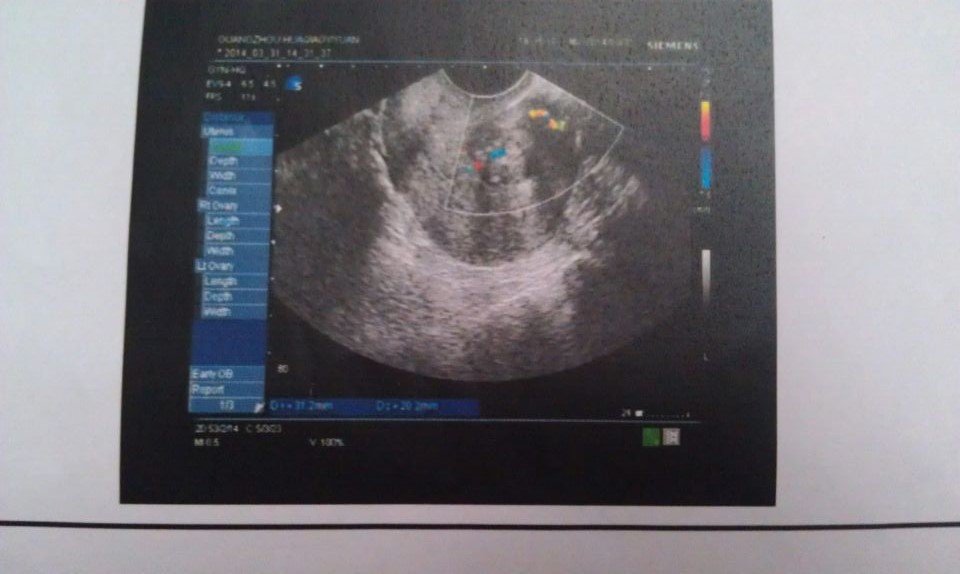

病情分析: 你好,看你这次检查是有患了子宫肌瘤的病情了,那看现在子宫肌瘤不是很大,到也不用进行手术治疗的 指导意见: 如果说你现在这时身体上也没有不适的症状,平时来月经方面都是正常的话,那也可以先考虑怀孕的,并在怀孕生产后在治疗子宫肌瘤方面也行